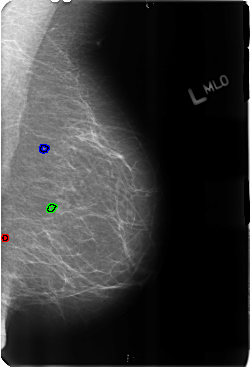

B_3167_1.LEFT_MLO

FILE: B_3167_1.LEFT_MLO.OVERLAY

TOTAL_ABNORMALITIES 3

ABNORMALITY 1

LESION_TYPE CALCIFICATION TYPE SKIN-PUNCTATE DISTRIBUTION N/A

ASSESSMENT 2

SUBTLETY 3

PATHOLOGY BENIGN_WITHOUT_CALLBACK

ABNORMALITY 2

ABNORMALITY 3